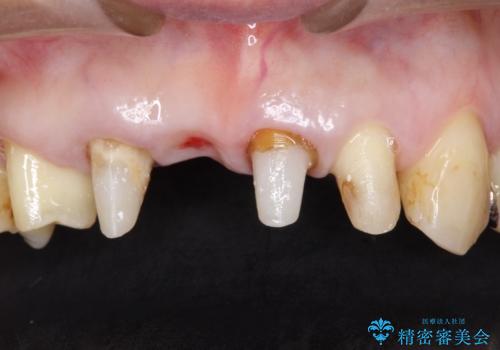

治療の順序は

①保存不可の歯の抜歯・根管治療

②矯正治療

③セラミックの装着

という流れで行いました。